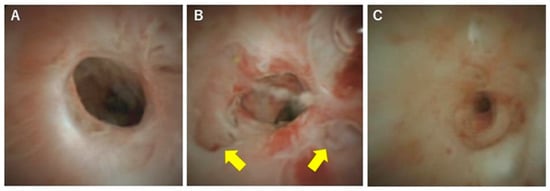

4. POCS for Diagnosing PSC

5. The Phases of PSC and Cholangioscopic Findings in Each Phase

6. Diagnosis and Classification of PSC Using POCS